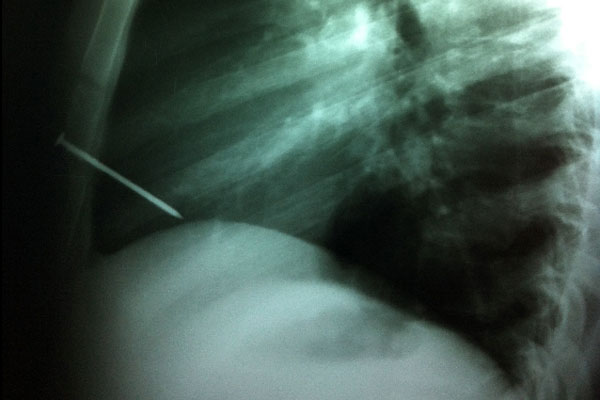

La radiografía muestra el clavo en el tórax. Foto: Ministerio de Salud de la Nación

Los profesionales explicaron que el clavo, de ocho centímetros de largo, atravesó el esternón y el ventrículo derecho del corazón, y quedó alojado en la cavidad cardíaca. «En el quirófano se procedió a la apertura del hueso del esternón con mucho cuidado porque se corría el riesgo de chocar con el clavo y agrandar la herida cardíaca», relató Nahín, y añadió que «y ya con el elemento perforante a la vista realizamos la extracción manual del cuerpo extraño, que se había incrustado en la cara anterior del ventrículo derecho».